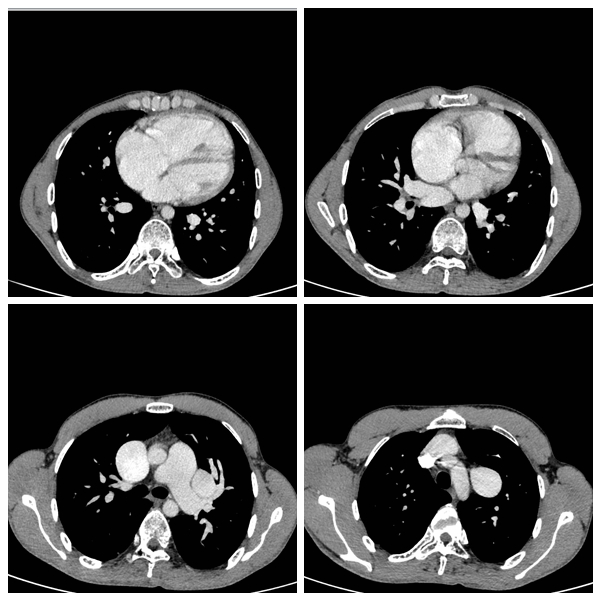

图一可见房间隔缺损;图二可见肺静脉与左房未直接相连;图三图四可见异位引流血管(垂直静脉)。

26岁的桃源小伙文某因体检发现心脏杂音于当地医院检查心脏彩超,怀疑先天性心脏病、房间隔缺损,但没有明确诊断。文某为进一步诊断及治疗便在家属的陪同下来到湘雅常德医院心胸外科就诊,心胸外科黄日茂主任接诊后查体发现患者口唇和四肢末梢轻度紫绀,左前胸壁明显隆起;完善血管CT及心彩超检查提示:房间隔缺损,且左右肺静脉完全错位。本应开口在左心房的左右肺静脉通过——垂直静脉搭到无名静脉上,经无名静脉从上腔静脉回到右心房,造成右心房扩大,左心房因为没有得到足够的血液而导致发育不良。 确诊病人为完全性肺静脉异位引流患者,且合并房间隔缺损及三尖瓣关闭不全。黄日茂主任表示这是一种严重复杂且少见的先天性心脏病,发病率约百万分之一,且患者能活到成年者更加罕见,主要“得益”于患者同时合并了先天性房间隔缺损,使得错误流入右心房的血能部分流入正常的左心房,但随着患者年纪越大,运动量及血容量增加,这种畸形的供血方式不能满足机体的正常需求,并可能导致上腔静脉严重扩张。若不尽早行手术治疗,最终会因为严重肺动脉高压而失去手术机会。